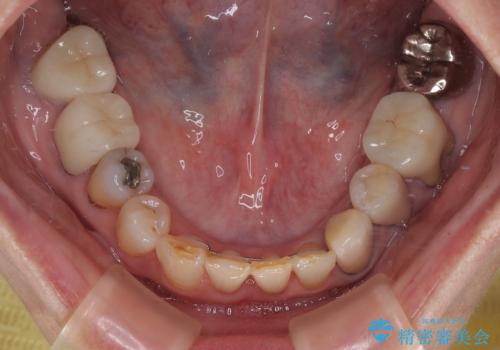

デコボコが強いため、ブリッジや残根となっている部分のスペースを利用して歯列を整え、変色や欠けている歯をオールセラミッククラウンによる補綴治療を行うこととしました。

歯肉移植などによる前歯部の歯肉ライン改善を提案しましたが、口を開けたときにほとんど見えないので気にならないとのことで、特に処置を行うことなく補綴治療を行いました。